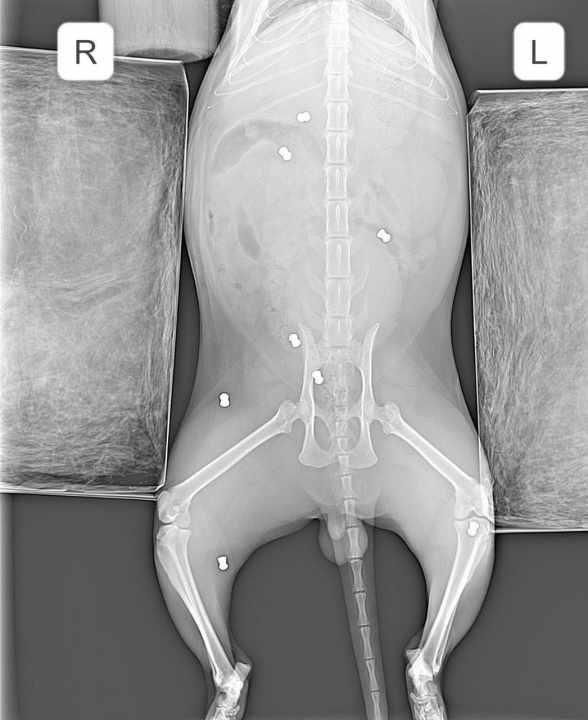

В Арзамасе неизвестный расстрелял кота из «воздушки». Кот ушёл гулять, а вернулся со множеством пуль по всему телу.

Ветеринар заключил, что пушистика привязали, чтобы он не убегал, и стреляли в него. Бедняга сейчас в больнице в тяжёлом состоянии.